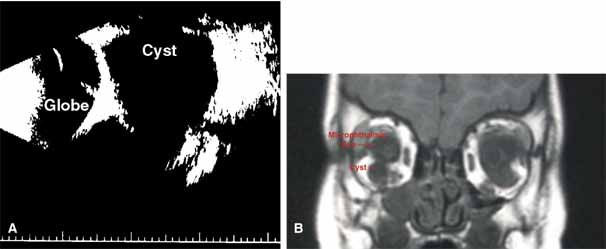

“Microphthalmia with cyst” refers to cases of colobomatous microphthalmia with a posterior eye wall defect through which a cyst lined with neuroectodermally derived tissue protrudes into the orbit. These cysts may be small and only detected by imaging (Fig. 2); sometimes, they may be large enough to cause progressive proptosis. Most cases are isolated, but familial occurrences have been reported.67–69 Inheritance is likely autosomal recessive. Depending on the size of the cyst, its appearance, and the visual potential of the microphthalmic eye, these cysts may be managed by observation, excision with or without enucleation, and/or aspiration.70 Aspirated cysts tend to reaccumulate fluid. Socket expansion improves cosmesis.

Fig. 2 A. B-scan ultrasonogram shows microphthalmia with cyst. B. MRI demonstrates cyst located on the inferior aspect of a microphthalmic eye.